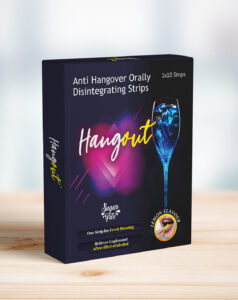

Lifestyle Products

Hangout Oral Films- Hangout Oral Films Gives Refreshing Next Morning. Hangout Contains “Milk Thistle And Ginger”, A Bio Active Ingredients Which Is Clinically Proven Anti-Oxidant. It Helps In Liver Protection By Reducing Toxicity Caused By Alcohol. It Also Prevents Hangover Effects Arising From It. It Will Also Help To Maintain Muscle And Nerve Function.

Lifestyle Products

Hangout Oral Films- Hangout Oral Films Gives Refreshing Next Morning. Hangout Contains “Milk Thistle And Ginger”, A Bio Active Ingredients Which Is Clinically Proven Anti-Oxidant. It Helps In Liver Protection By Reducing Toxicity Caused By Alcohol. It Also Prevents Hangover Effects Arising From It. It Will Also Help To Maintain Muscle And Nerve Function.